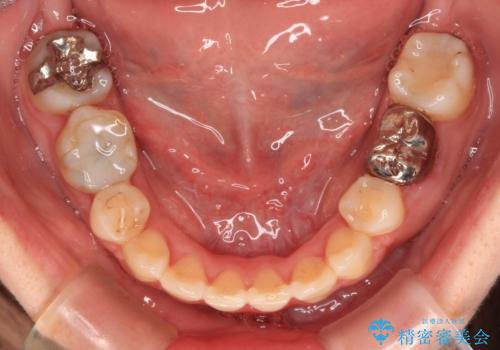

- 八重歯やデコボコを気にして来院された患者様です。

お住まいから船での通院となることから、補助装置を使用しながらインビザラインにて上下左右第一小臼歯4本を抜歯した矯正治療を行うこととしました。